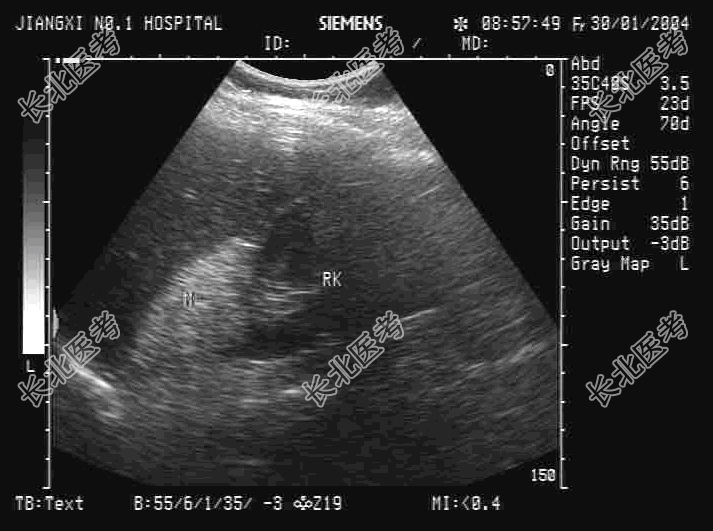

- 单项选择题某患者没有明显不适,根据其肝右叶-右肾区超声检查如图, 最可能的诊断为

A、正常图像

B、肾脓肿

C、肾上腺腺瘤

D、肾上腺嗜铬细胞瘤

E、肾上腺髓样脂肪瘤